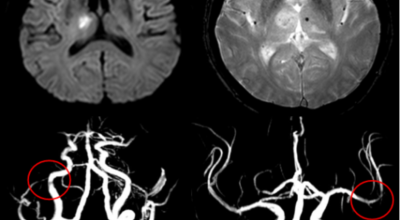

뇌경색의 가장 흔한 원인은 고혈압, 당뇨, 고지혈증 등으로 인해 뇌에 혈액을 공급하는 혈관에 뇌혈류가 차단되는 경우와 그 밖에심장 부정맥, 심근경색의 후유증 등으로 인해서 심장에 혈액이 응고된 상태가 되고 이 혈전이 혈류를 따라 이동하다가 뇌혈관을 막아 뇌졸중이 나타나는 경우도 있어요.

큰 뇌혈관이 막힌 경우라면 발생한지 4시간 반 안에 정맥 내로 혈전 용해제를 투여해 막힌 혈관을 뚫어주게 되고 6시간 이내라면 직접 동맥 내 시술을 통해 혈관을 막은 혈전을 직접 제거하는 혈전제거술을 시행하게 되는데요.